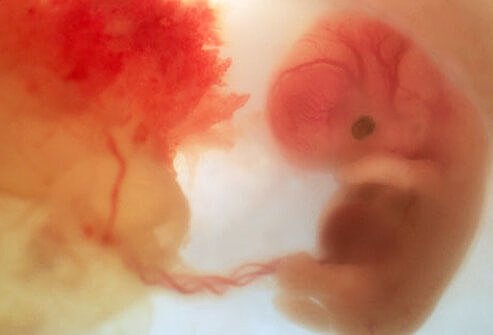

Fetal Development

• Second Month

Second Month

The zygote is about 1/4 inch long and has distinct, slightly webbed fingers. Face, eyes ears and limbs have developed. Veins are clearly visible. The heart has divided into right and left chambers. Zygote changes into an embryo at the end of eight weeks.